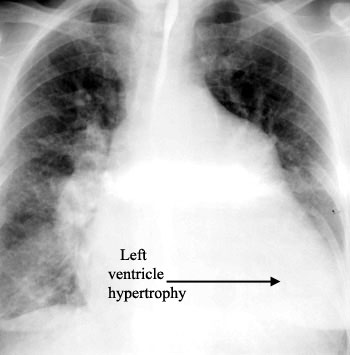

During a routine physical exam for participation in interscholastic sports, the physician noted that E.S., a twelve-year-old boy, had a long continuous heart murmur at the second intercostal space near the left sternal border. A systolic thrill was also noted in the same region. When questioned, the patient's mother recalled that E.S. had periods of cyanosis and breathlessness as an infant, but that his previous pediatrician said that the murmur and the symptoms were nothing to be concerned about. E.S. also mentioned that he tires easily during physical activity. Chest films and Doppler ultrasound were ordered . The radiographs indicated slight left ventricular hypertrophy, and ultrasound revealed a patent ductus arteriosus. E.S. was scheduled for surgery to ligate the ductus arteriosus. The surgery resulted in successful ligation of the ductus arteriosus; however, E.S. experienced hoarseness when speaking following the procedure. Laryngoscopy revealed paralysis of the left vocal fold.

Initial consequences of a patent ductus arteriosus include cardiac failure and pulmonary edema in infants (accounting for the cyanosis and breathlessness experienced by E.S.); however, a patent ductus arteriosus is often compatible with survival to adulthood. Cardiac failure (which may be the reason for the slight left ventricular hypertrophy observed in E.S.) and bacterial endocarditis are common complications. If left untreated, pulmonary hypertension develops, resulting in hypertrophy of the right ventricle and eventually in a reversal of flow (to right-to-left), leading to cyanosis, clubbing of fingers and toes, and polycythemia due to systemic circulation of large amounts of deoxygenated blood, as well as right heart failure. Clearly, E.S.'s first pediatrician should have been more concerned about E.S.'s condition.